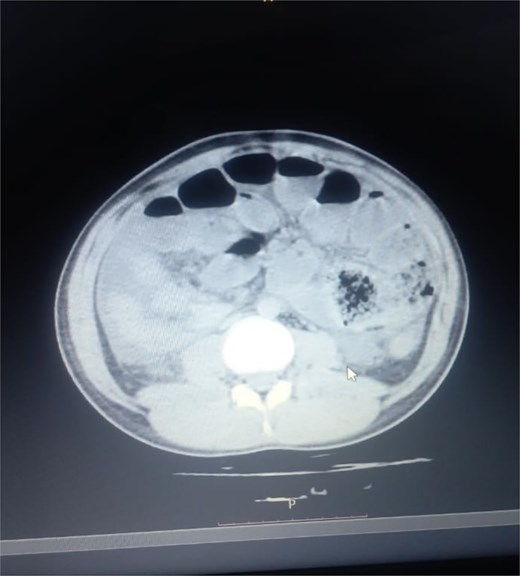

Initial radiographic evaluation with a plain abdominal X-ray confirmed the clinical suspicion of acute intestinal obstruction, demonstrating multiple air-fluid levels and diffuse small bowel dilatation (Fig. 1). To further delineate the underlying etiology, a contrast-enhanced computed tomography (CECT) scan was performed; providing critical diagnostic information it revealed, in the right iliac fossa, a striking encapsulation of the small intestine loops within a sac-like membrane, accompanied by ascites. This constellation of findings formed a pathognomonic cocoon-like structure (Fig. 2). Furthermore, the CECT identified a concurrent gut malrotation, evidenced by a left-sided displacement of the colon (Fig. 3). Laboratory findings showed an elevated total leukocyte count (TLC) of 21 000, indicative of inflammation, while other parameters were within normal limits. The patient underwent an exploratory laparotomy. Intraoperatively, the abdominal viscera were encased within a thick fibrous membrane (Fig. 4), containing ascitic fluid. The membrane was incised, adhesiolysis was performed, and the entrapped small bowel loops were released, and then a kink in the small intestine causing obstruction was identified and corrected. Additionally, the appendix was found to be secondarily involved in the encapsulating process. It was encased in the dense fibrocollagenous membrane, forming an inflammatory mass consistent with chronic serositis and localized fibrosis, rather than a classic acute appendicular phlegmon. Based on this intraoperative assessment that the mass was a manifestation of the cocoon’s chronic inflammation, a simple appendectomy was performed instead of a more extensive right hemicolectomy. This procedure was necessary to achieve complete release of the entrapped bowel, remove this localized inflammatory focus, and obtain a specimen for histopathology to definitively rule out a primary appendiceal pathology as a secondary cause of the peritonitis. Furthermore, ascitic fluid analysis showed no bacterial or mycobacterial growth, ruling out tuberculosis and the histopathological examination confirmed the fibrocollagenous nature of the membrane. The patient recovered well postoperatively and was discharged on the sixth day with advice for a follow-up after 2 weeks. At the follow-up visit, he reported no symptoms, and abdominal imaging confirmed the absence of obstruction. Histology further confirmed the benign fibrous nature of the membrane, with no signs of malignancy.

Abnormal positioning of encapsulated small bowel. This axial CT view, taken at a lower abdominal level, illustrates the profound anatomical derangement. The entire cluster of small bowel loops is seen encased and displaced into the right iliac fossa, a finding consistent with the combined effects of the cocoon membrane and the patient’s gut malrotation.